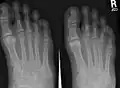

Podiatry